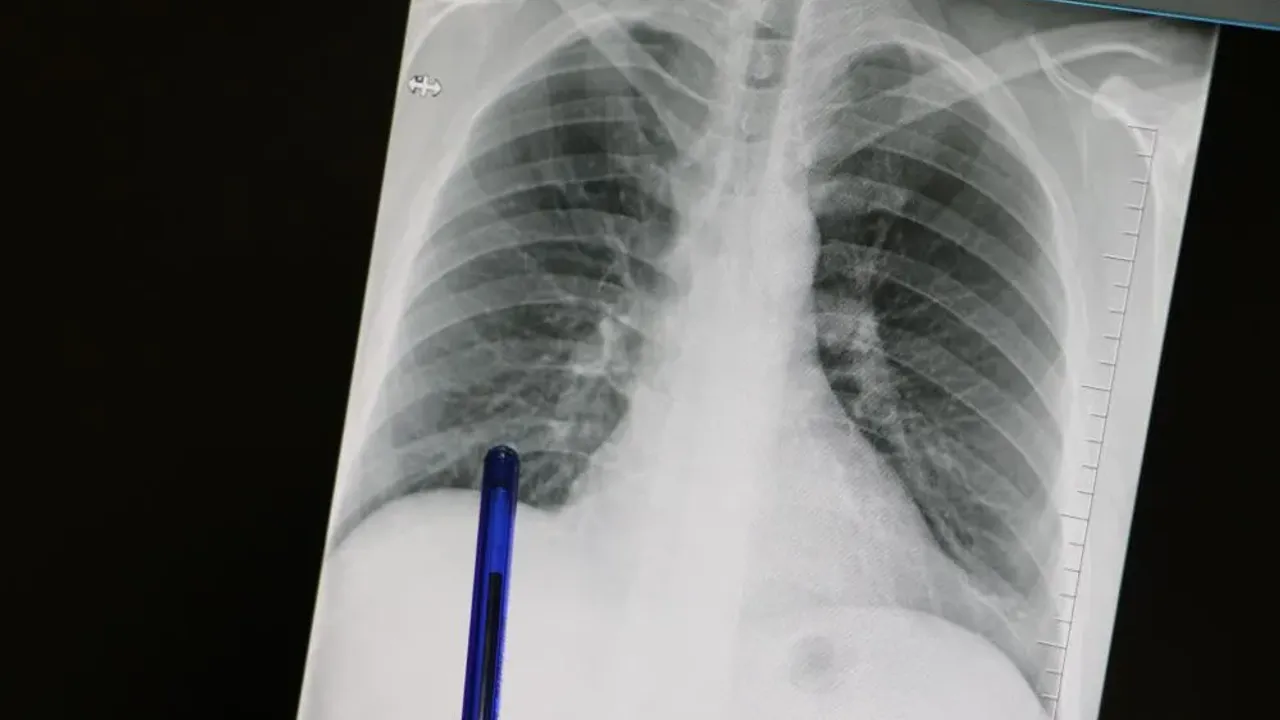

Kasım ayı, Türkiye’de ve dünyada hayati bir konuya dikkat çekiyor: Akciğer Kanseri Farkındalık Ayı. Akciğer dokusundaki hücrelerin kontrolsüz çoğalmasıyla ortaya çıkan ve tüm kansere bağlı ölümlerin en sık nedeni olan bu sinsi hastalık, basit görünen semptomların arkasına gizlenebiliyor.

Medicana Sivas Hastanesi Göğüs Hastalıkları Uzmanı Dr. Büşra Yayla Yerlikaya, pek çok kişinin önemsemediği öksürük ve balgam gibi belirtilerin, ne yazık ki akciğer kanserinin ilk habercisi olabileceğini vurguladı. Dr. Yerlikaya, "Bu hastalık, ne yazık ki genellikle erken evrede belirti vermediği için geç tanı alabilmekte ve bu da tedavi şansının azalmasına sebep olabilmektedir," uyarısında bulundu.

Hastalık Sinsice İlerliyor: Erken Evrede Belirti Vermiyor